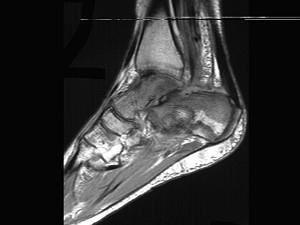

问题 男,28岁,踝部肿痛,结合图像,最可能的诊断是 ( ) .

选项 A、跟骨结核 B、踝关节类风湿关节炎 C、跟骨骨髓炎 D、踝关节滑膜炎 E、未见异常

答案 C